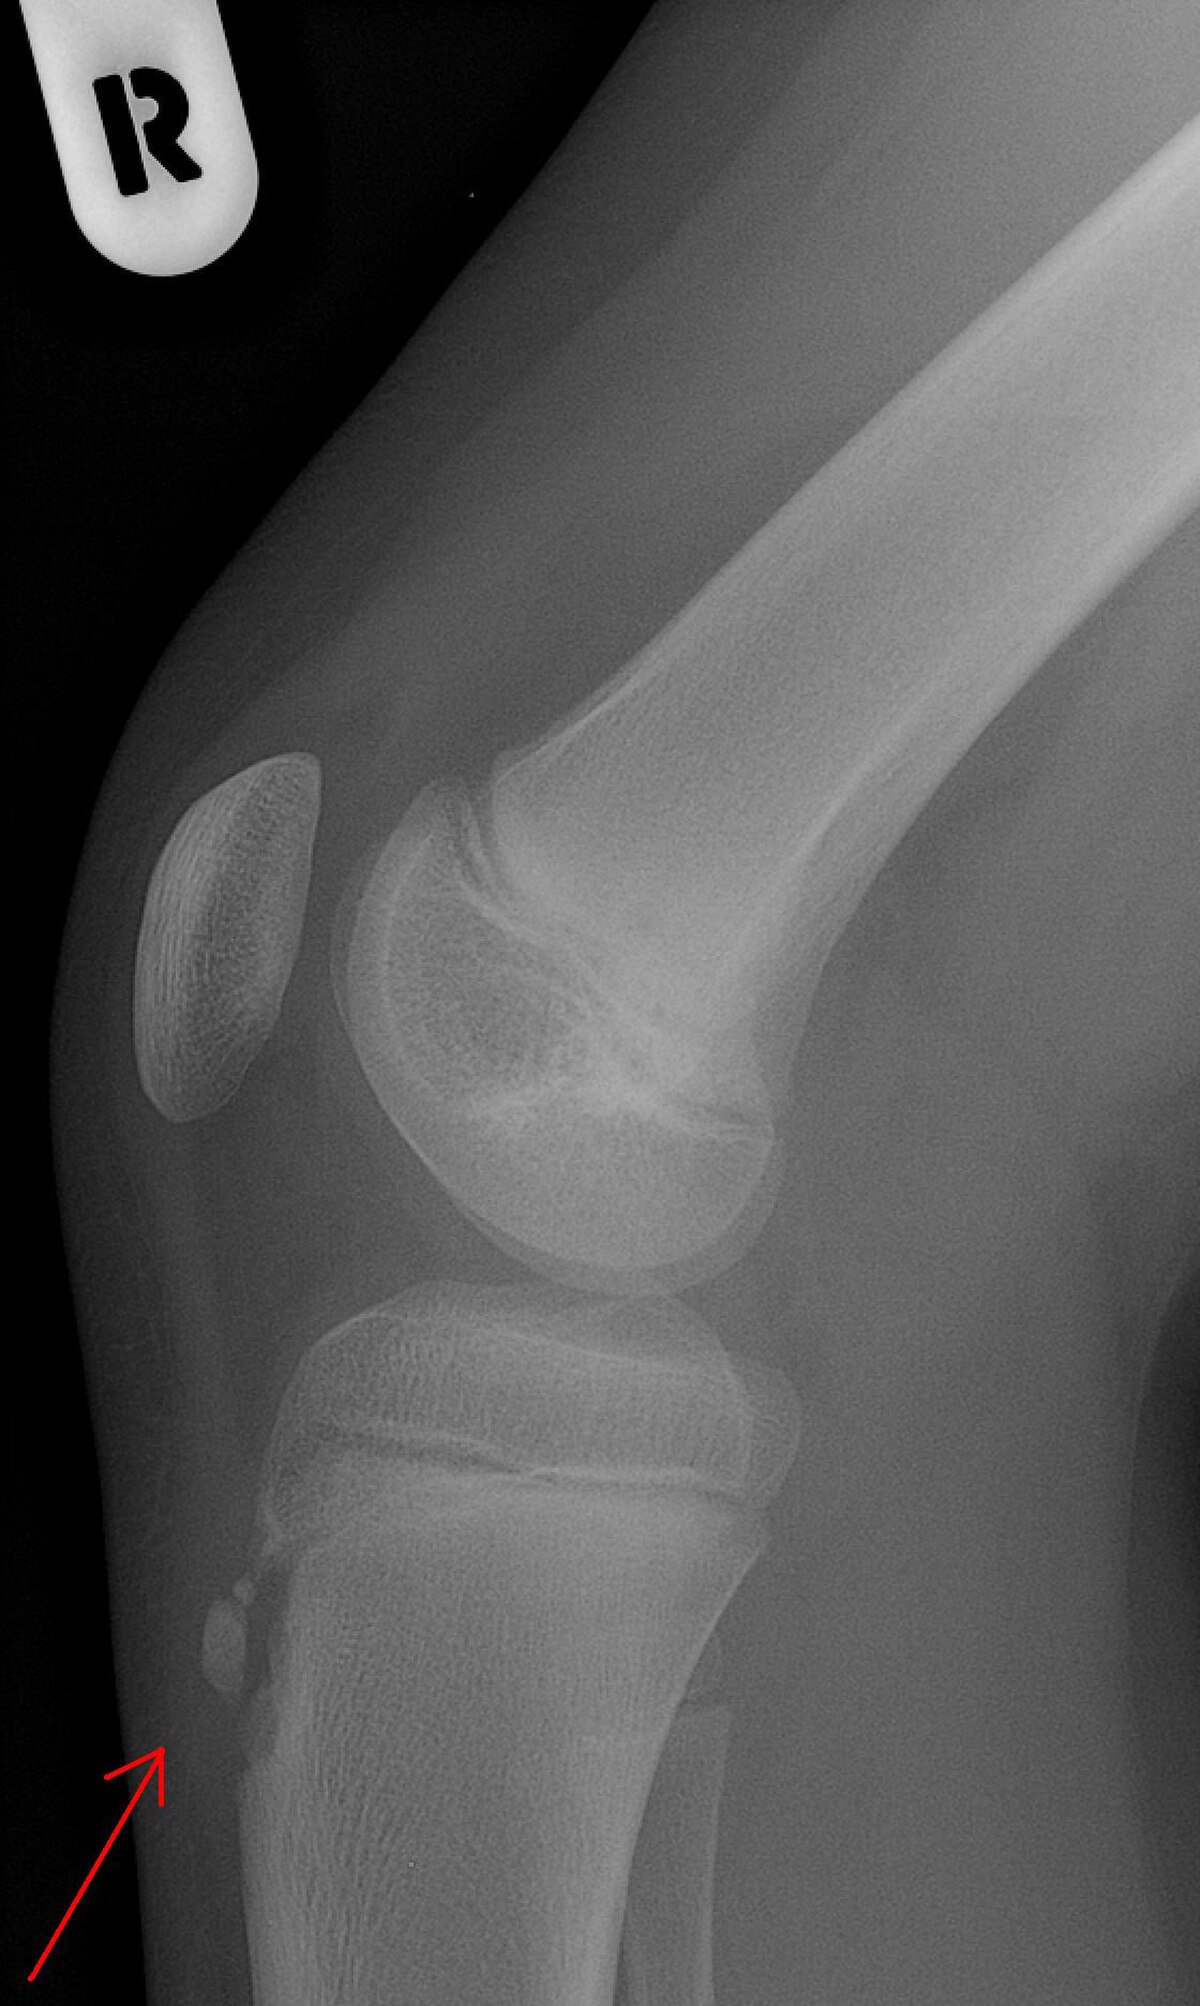

Une radiographie n'est pas nécessaire notamment lorsque le tableau clinique est évocateur et que les douleurs sont bilatérales. Elle peut être utile pour éliminer une autre pathologie si les douleurs sont unilatérales, atypiques ou rebelles au traitement. Initialement on retrouve un soulèvement de la tubérosité tibiale antérieure avec élargissement de son cartilage de croissance; dans les stades plus évolués, la TTA est fragmentée et on peut voir parfois des calcifications dans le ligament rotulien.